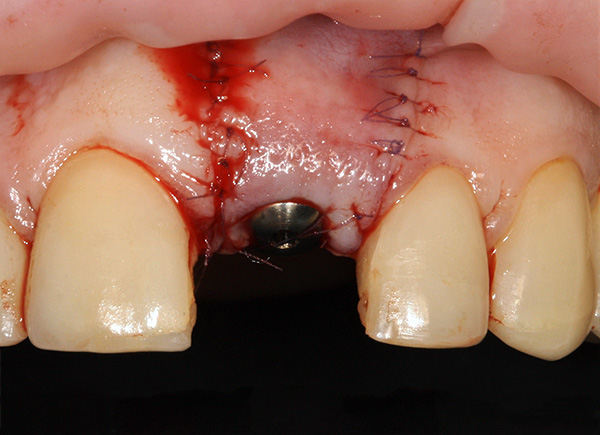

Em seguida, o retalho gengival é cortado e reclinado, um implante é inserido no orifício e o material ósseo granular é introduzido para a regeneração óssea:

Em seguida, a ponta da gengiva retorna ao seu lugar e é fixada com uma sutura: